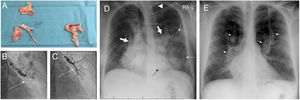

Patient 3 was a 46-year-old male with chronic obstructive pulmonary disease and CTEPH diagnosed at the age of 43. PEA was performed in 2017, and subsequently included in our BPA programme. He maintained triple vasodilator therapy and domiciliary oxygen. He also had history of critical pneumonia requiring invasive ventilation. In April 2020, he was admitted to hospital with high fever, mild dyspnoea and myalgias related to COVID-19 bilobar pneumonia (Fig. 1). CRP was remarkably high (28.3mg/dL) but SARS-CoV-2 PCR was negative, other viral panel and blood cultures were negative and there was no sign of bacterial superinfection. The epidemiological context, clinical presentation, lab results and radiographic pattern led to assume a false negative, and he was managed as COVID-19, with excessive inflammation governing the clinical picture. Accordingly, steroids and tocilizumab were prescribed along with antibiotics, with excellent response over the first two days. Hospital discharge was postponed due to readjustments on prostacyclin-administration route.

Images from patient 3. A. Material removed from the pulmonary vasculature by pulmonary endarterectomy. B. Pulmonary angiography showing occlusion (arrow) of the anterior segmental artery for the left superior lobe prior to percutaneous treatment of this region. C. The anterior segmental artery for the left superior lobe is recanalized after balloon pulmonary angioplasty (arrow). D. Chest X-ray on admission showing Ill-defined consolidations in medium and inferior left pulmonary fields (thin arrows). Note the dilation of the main pulmonary arteries (thick arrows) and the sternotomy wires. Interestingly, the patient carries a ventriculoperitoneal shunt (arrowhead). E. Chest X-ray at discharge. Complete clearing of lung opacities can be seen. Dilation of both pulmonary arteries is better recognized (arrows).